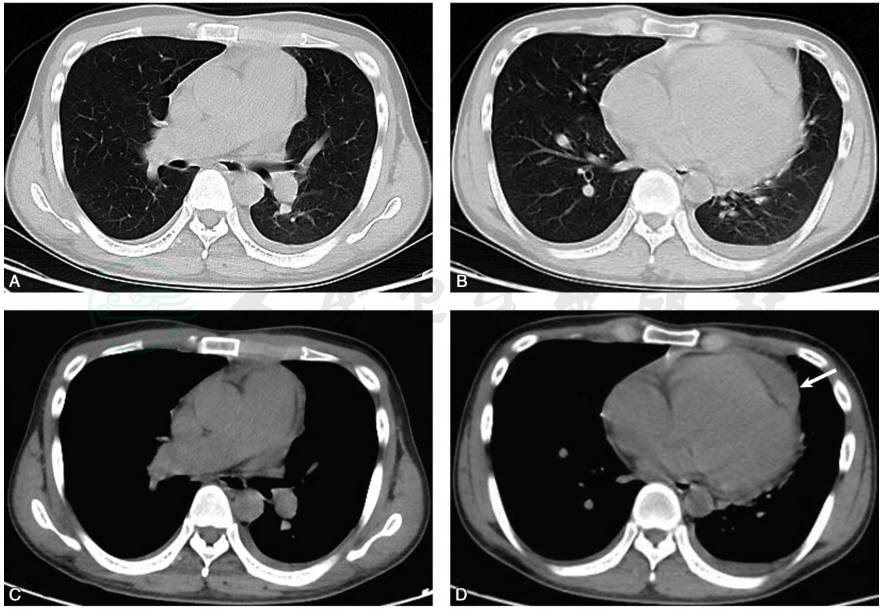

胸部CT平扫:冠脉钙化,心包积液,两侧胸腔积液(图1)。

图1 患者胸部CT扫描示:双侧肺野清晰(A、B);纵隔窗示肺动脉主干增宽伴双侧胸腔少量积液(C);心胸比例显著增大,右房和右室显著增大,心包少量积液(白箭),左房缩小,左室受压(D)